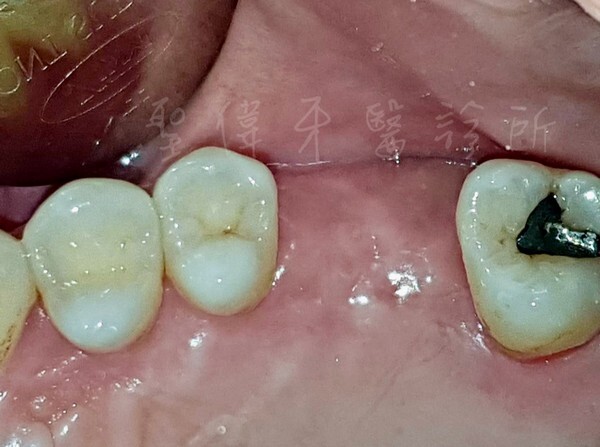

▼少的還是大臼齒

咬東西的時候有時候被食物磨到

或是有殘渣卡到

真的是蠻不舒服的